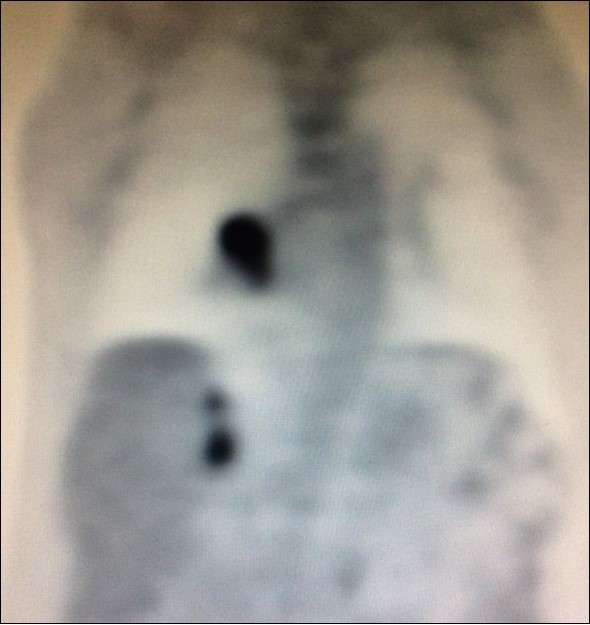

There is limited understanding of the efficacy of surgical resection because of low incidence of isolated adrenal metastasis in patients with stage IV NSCLC. Some series showed that the time from diagnosis of primary lung cancer diagnosis of adrenal metastasis - disease-free interval (DFI) – is a prognostic factor6. Synchronous metastases (Figure 4), defined as a DFI of 6 months or less, has been associated with a poor prognosis.

Figure 4.PET CT showing simultaneous uptake on right lung mass and 2 ipsilateral adrenal nodules.

PET CT showing simultaneous uptake on right lung mass and 2 ipsilateral adrenal nodules.